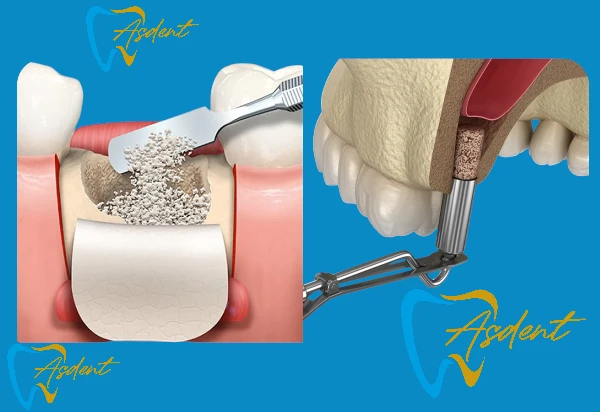

Костный трансплантат и поднятие синуса + пакет имплантатов в Турции

- Специальное решение для пациентов с недостаточным объемом костной ткани.

- Процедура костной пластики, мембраны и поднятия синуса.

- Затем установка имплантата.

- Последующее наблюдение, включая прием лекарств и контроль за процессом заживления.

Преимущества: Постоянное решение даже для пациентов с недостаточной костной структурой для имплантатов.